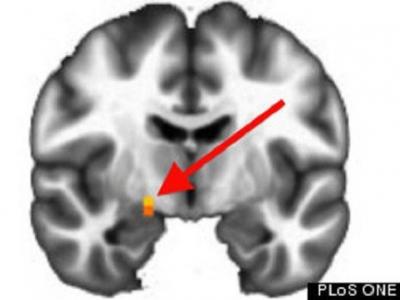

通过大脑扫描可区分政治倾向

共和党大脑右侧的杏仁核表现出明显的活跃性 这项研究检查了35位男性和47位女性的...